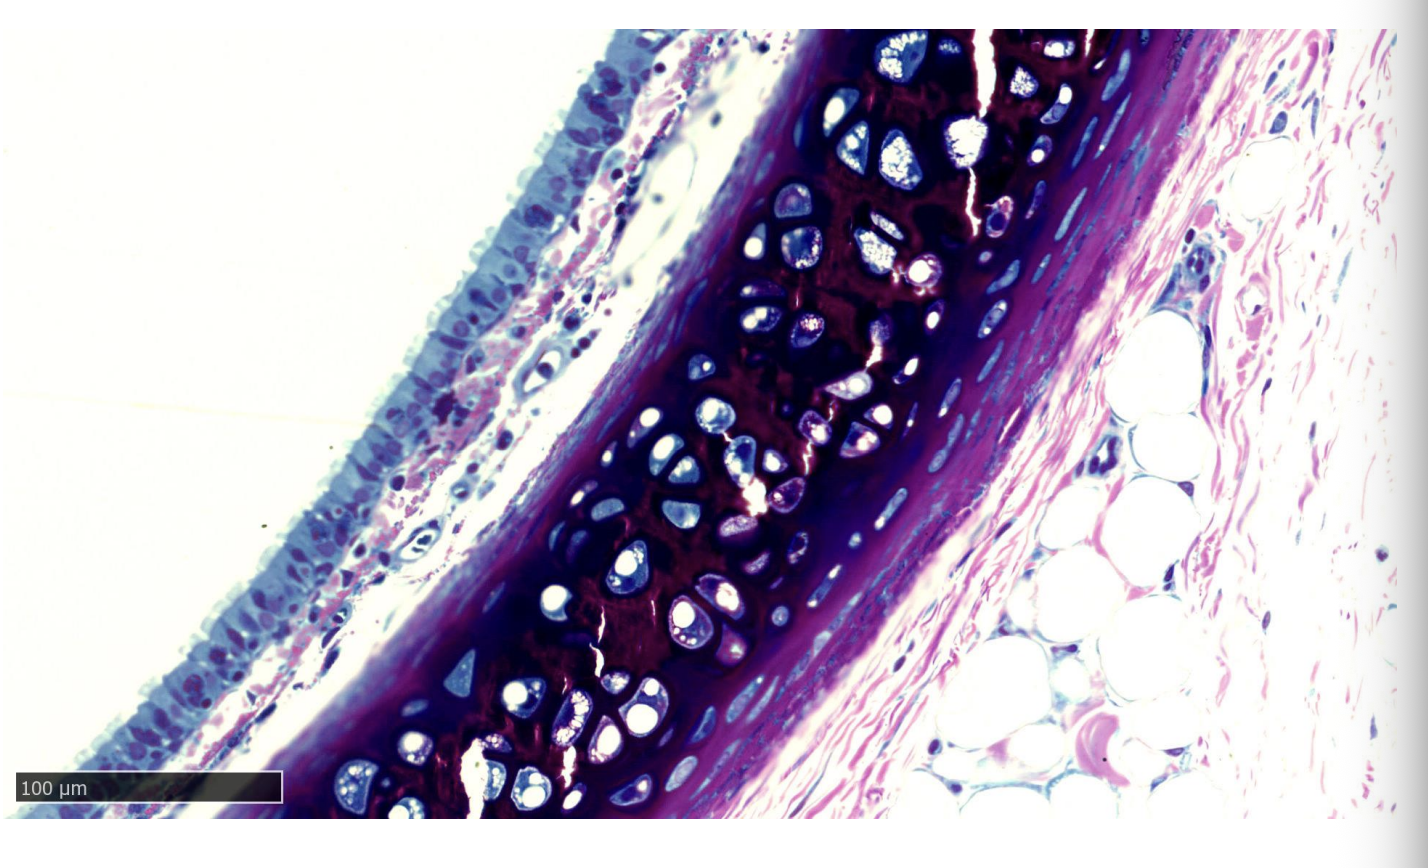

Oesophagus and Trachea of rat

Part of Liver cell→ rat

Identify

The cell membrane

The nucleus and nuclear envelope

Rough and smooth endoplasmic reticulum

Ribosomes

Golgi apparatus

Mitochondria

Vesicles

Lysosomes

Glycogen granules

Add the drawing of these that identify what this is